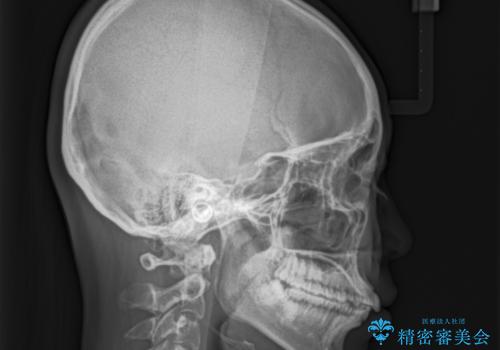

【インビザライン】前歯が出ているのを治したい

- 前歯が出ていることを主訴に来院されました。

前歯の突出感が改善され、満足していただきました。